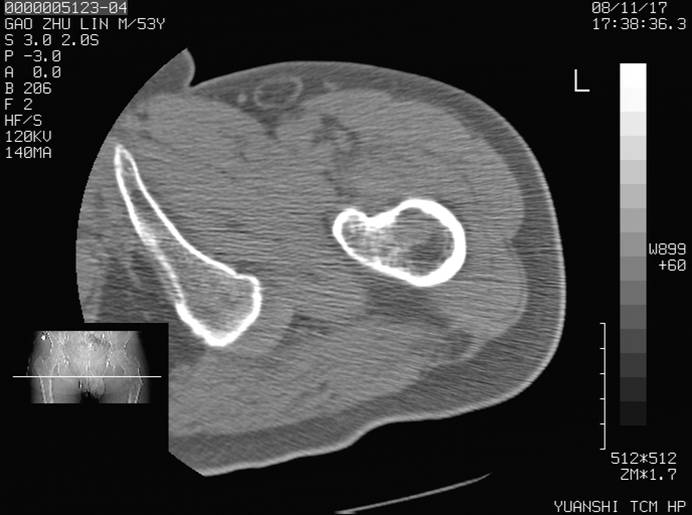

标题: CT16696:M53Y,左股骨上段骨折。 [打印本页]

标题: CT16696:M53Y,左股骨上段骨折。

左股骨上段外伤1个小时,左股骨上段疼痛。村医以腰椎间盘病变给以按摩及理疗数天。

图像不太清楚,左股骨上段外伤性骨折?病理性骨折?

左股骨上段粉碎性骨折

左股骨上段粉碎性骨折;建议上传骨窗看看是不是病理性的啊!

左股骨上段粉碎性骨折,不排除病理性骨折可能。

考虑骨肉瘤伴病理骨折

考虑:骨肉瘤伴病理骨折.

病理性骨折,考虑转移所致.